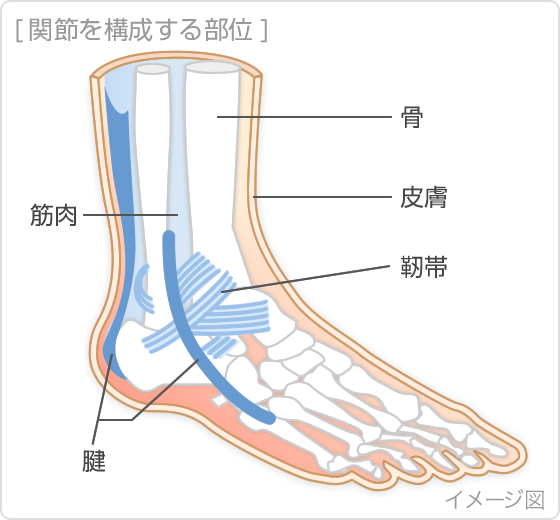

捻挫で湿布を使用する期間はいつまで? 冷やす温めるが大切です! スポンサーリンク 捻挫というのは靭帯が損傷する怪我です。 靭帯を損傷すると痛みだけでなく、腫れや内出血を伴いこともあります。 きちんと処置することによって早期完治だけでなく再発を防ぐことや癖になることを防ぎます。 この場合に湿布を使用する期間というのはいつまででしょうか

捻挫 ねんざ の症状 原因 くすりと健康の情報局